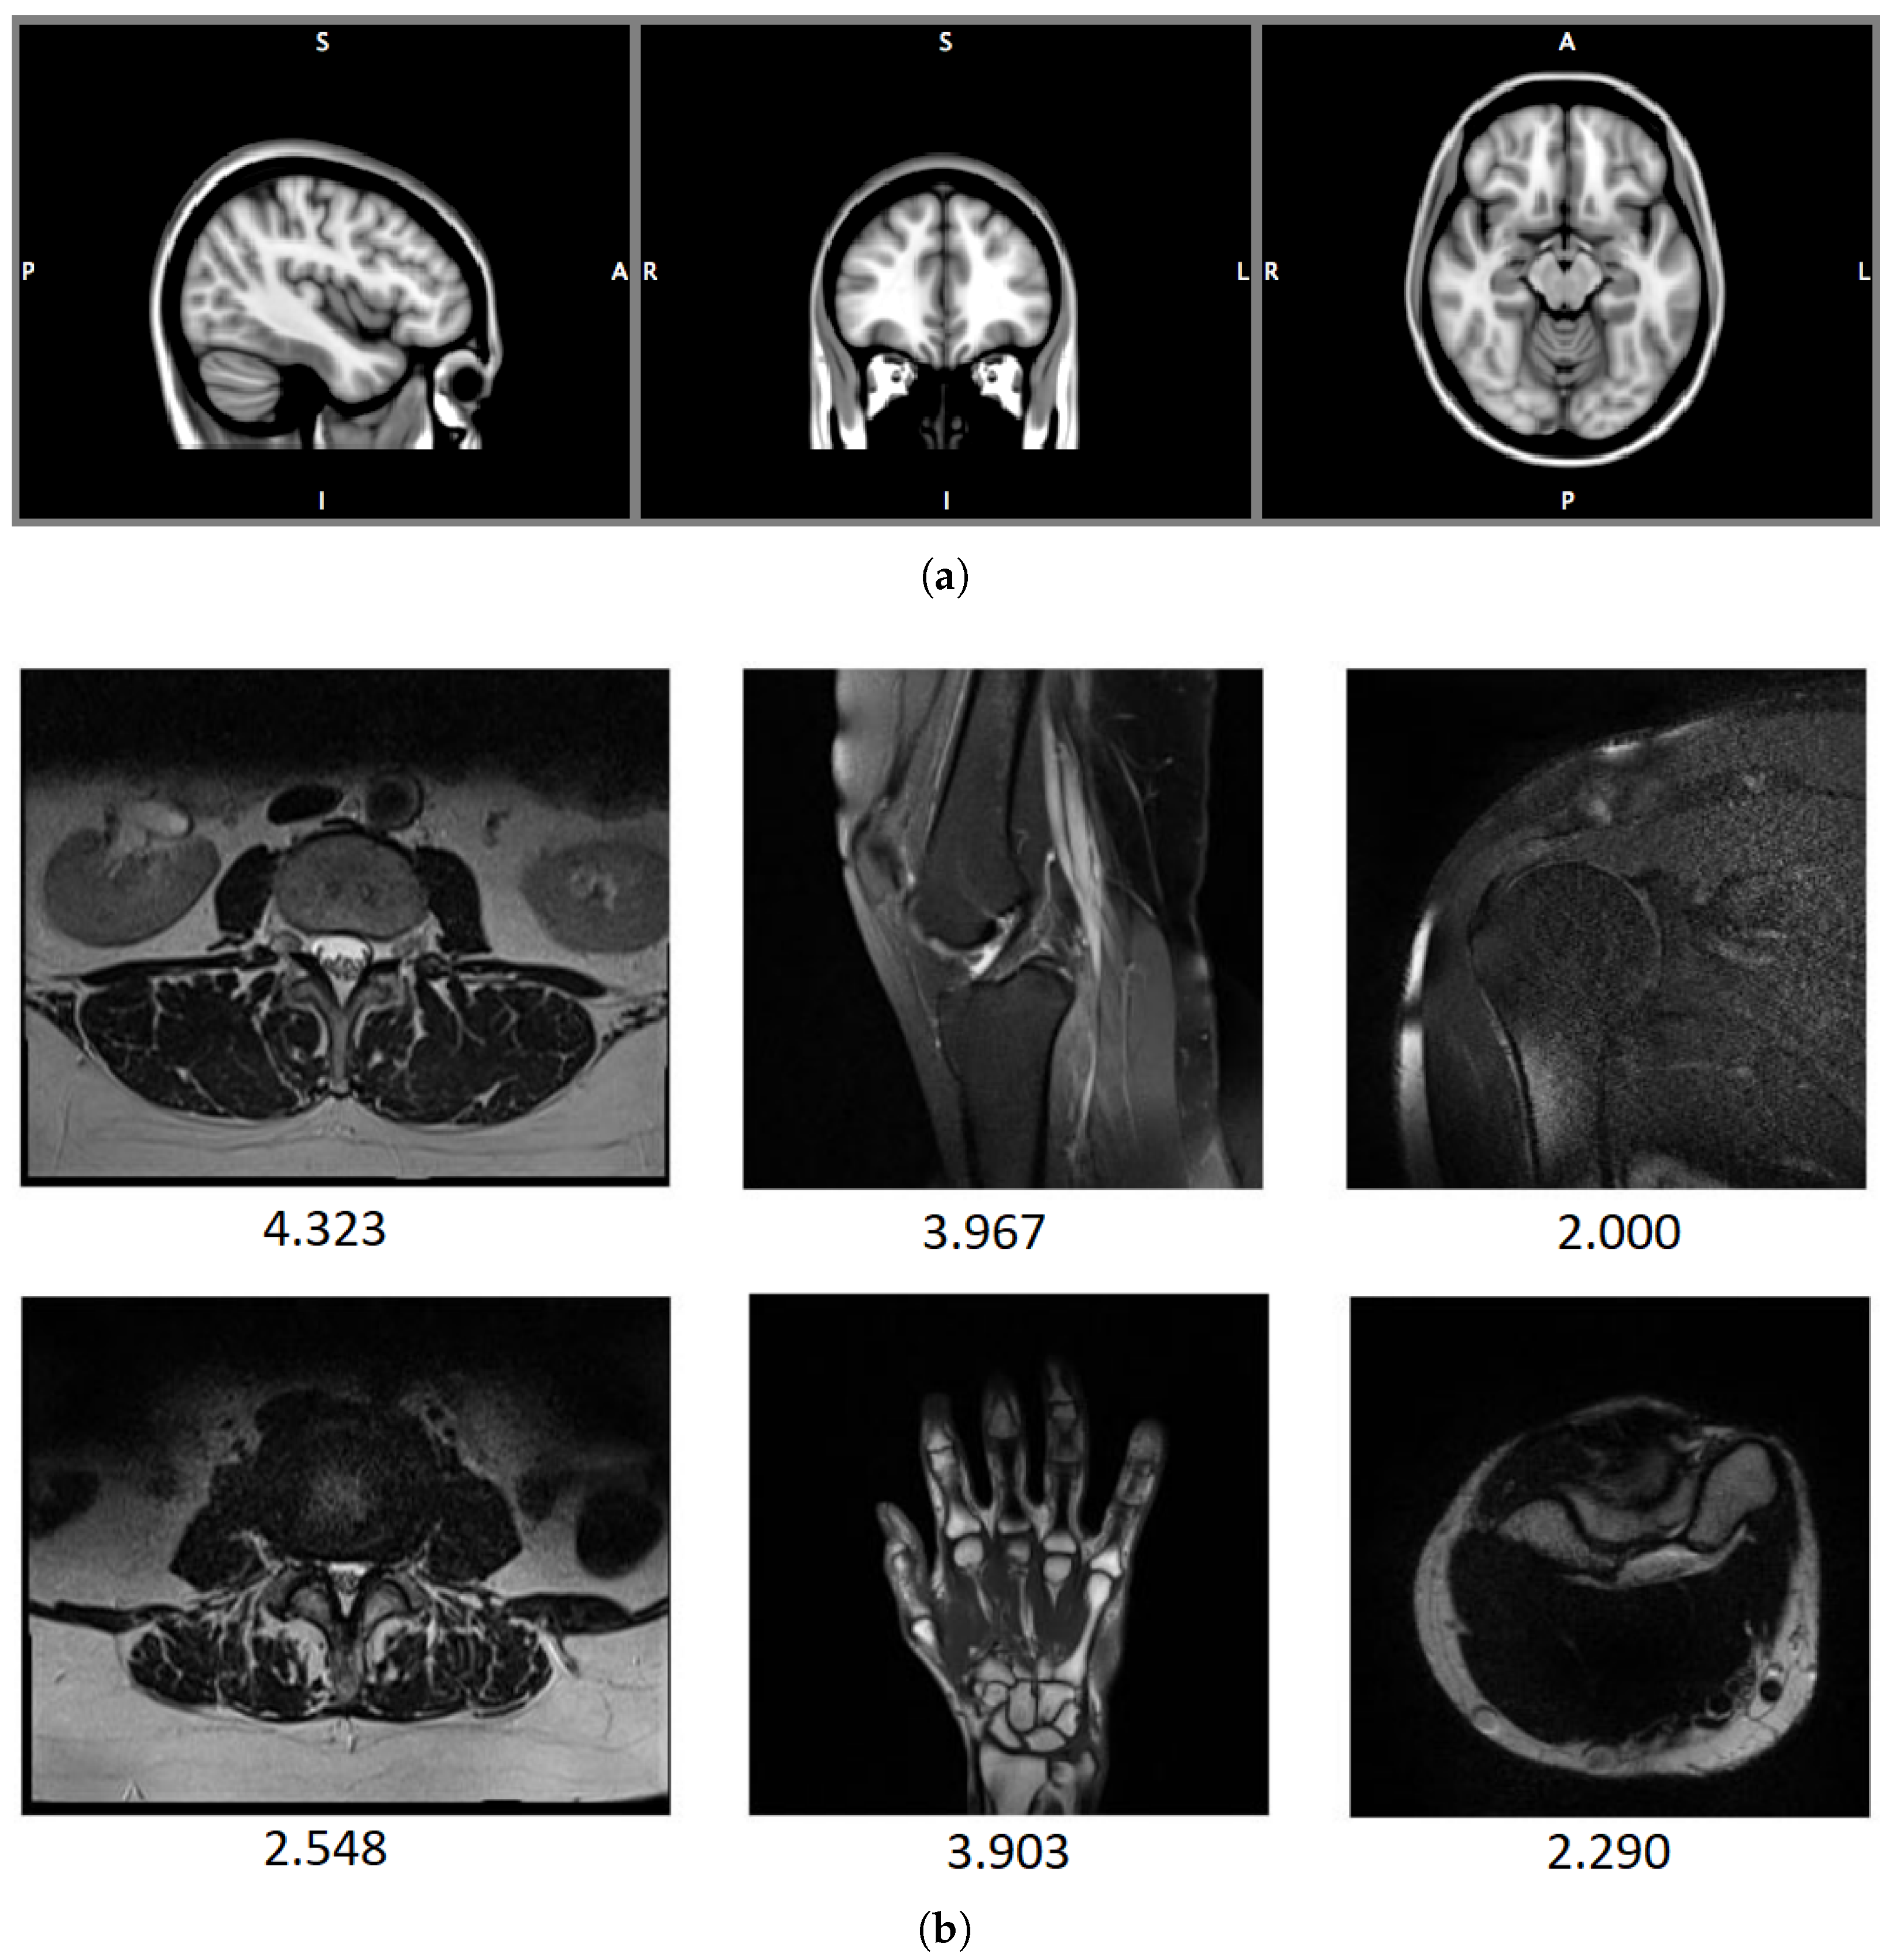

4.1.5. 1.5 T T2-Weighted MR Image Databases: DB1, DB2

| DB1 | 2020 | 70 | marosz.kia.prz.edu.pl/ENMIQA.html |

| DB2 | 2020 | 240 | marosz.kia.prz.edu.pl/NOMRIQA.html |